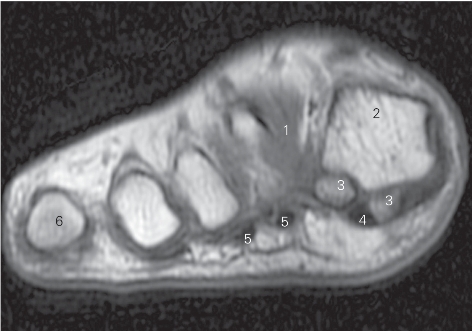

图5-54 经第一跖骨远端的横断层MR T1加权图像

1

长伸肌腱tendon of extensor hallucis longus

2 第一跖骨 1st metatarsal bone 3

收肌 adductor hallucis

4

展肌 abductor hallucis 5

短屈肌 flexor hallucis brevis

6

长屈肌 flexor hallucis longus 7 屈肌腱 flexor tendon

8 小趾展肌 abductor digiti minimi 9 第五跖骨 5th metatarsal bone

10

收肌横头 transverse head of adductor hallucis

11 骨间足底肌 plantar interossei 12 骨间背侧肌 dorsal interossei